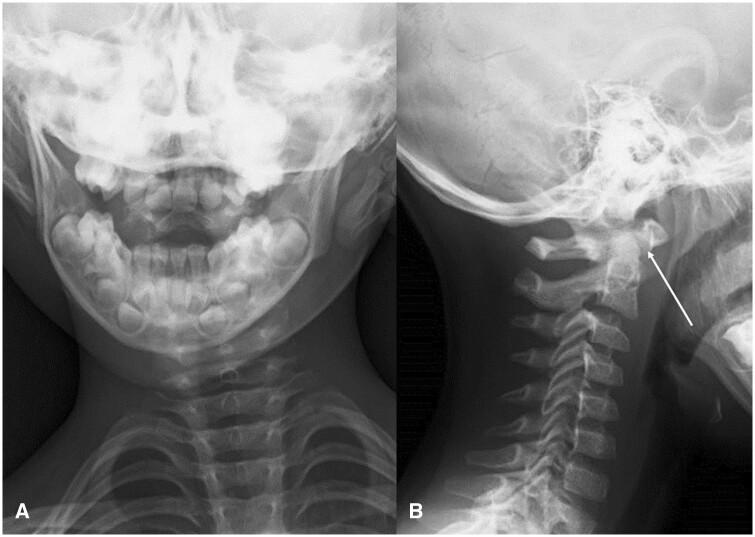

Various respiratory, musculoskeletal, gastrointestinal, neurological, and urinary complications have been reported in Kawasaki disease. Here, we describe a rare case of atlantoaxial rotatory fixation (AARF) associated with incomplete Kawasaki disease. The case is of a healthy 4-year-old Japanese boy who had a high-grade fever, lymphadenopathy, and torticollis diagnosed with incomplete Kawasaki disease. Intravenous high-dose immunoglobulin and oral aspirin quickly resolved his fever and improved his lymphadenopathy, but torticollis remained. On orthopaedic examination, torticollis was observed with a marked restriction of rotation, and an open-mouth anteroposterior cervical radiograph and a CT scan confirmed rotational dislocation at the dens axis (AARF). Cervical collar fixation was immediately started, and the torticollis gradually normalized within a week. AARF is defined as torticollis due to dislocation or subluxation of the atlantoaxial joint. The diagnosis of AARF is difficult with routine plain cervical radiographs in 2 directions alone, and an additional cervical open-mouth anteroposterior radiograph and a CT scan aid the diagnosis. AARF associated with Kawasaki disease is uncommon, and only 24 cases have been reported in the literature. AARF may occur in Kawasaki disease patients with cervical lymphadenopathy. Still, torticollis is often transient and may not be recognized or ignored by family doctors and paediatricians. Reduction of the atlantoaxial joint can often be achieved spontaneously or with conservative treatment such as a collar or neck traction, but treatment is difficult if the diagnosis is delayed. Therefore, family doctors and paediatricians need to suspect the onset of AARF if torticollis is observed during treatment for Kawasaki disease, perform plain cervical radiographs including open-mouth anteroposterior view and a CT scan of the cervical spine, and have orthopaedists immediately intervene to avoid invasive surgery.

川崎病已报告有各种呼吸、肌肉骨骼、胃肠道、神经和泌尿系统并发症。在此,我们描述一例与不完全川崎病相关的罕见寰枢椎旋转固定(AARF)病例。该病例为一名健康的4岁日本男孩,他出现高热、淋巴结病和斜颈,被诊断为不完全川崎病。静脉注射大剂量免疫球蛋白和口服阿司匹林迅速缓解了他的发热并改善了淋巴结病,但斜颈仍存在。经骨科检查,发现斜颈伴有明显的旋转受限,颈椎开口前后位X线片和CT扫描证实齿状突轴旋转脱位(AARF)。立即开始使用颈托固定,斜颈在一周内逐渐恢复正常。AARF定义为由于寰枢关节脱位或半脱位导致的斜颈。仅通过常规的两个方向的颈椎平片很难诊断AARF,额外的颈椎开口前后位X线片和CT扫描有助于诊断。与川崎病相关的AARF并不常见,文献中仅报道了24例。AARF可能发生在患有颈部淋巴结病的川崎病患者中。然而,斜颈通常是短暂的,可能未被家庭医生和儿科医生认识或忽视。寰枢关节复位通常可以自发实现或通过保守治疗如颈托或颈部牵引来实现,但如果诊断延迟,治疗会很困难。因此,如果在川崎病治疗期间观察到斜颈,家庭医生和儿科医生需要怀疑AARF的发生,进行包括开口前后位的颈椎平片和颈椎CT扫描,并让骨科医生立即介入以避免进行侵入性手术。